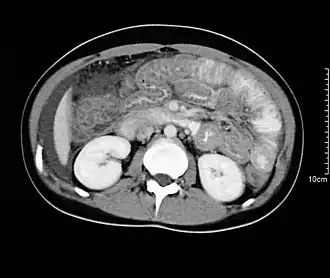

При исследовании печени, поджелудочной железы и жёлчных протоков ведущую роль занимают ультразвуковые исследования (УЗИ), компьютерная томография (КТ) и магнитно-резонансная томография (МРТ). При диагностике состояния пищевода распространено рентгеновское исследование с барием, при котором прохождение глотков бариевой взвеси регистрируется флюороскопически в реальном масштабе времени. Рентгенография пищевода применяется для выявления грыж пищеводного отверстия диафрагмы, опухолей, дивертикулов, стриктур, варикозного расширения вен, инородных тел. Рентгенография или рентгеноскопия с двойным контрастированием или без него применяется при исследовании желудка и двенадцатиперстной кишки с целью выявления язв, опухолей, стриктур, обтураций, контроля результатов оперативных вмешательств. Для диагностики опухолей кишечника, воспалительных заболеваний, причин непроходимости кишки, стриктур, обструкции применяется контрастная рентгенография, компьютерная или магнито-резонансная томография[28].

- Лучевая диагностика болезней ЖКТ

-

Магнито-резонансный томограф

Рентгенография пищевода с контрастной бариевой взвесью -

МРТ-изображение содержащих камни жёлчного пузыря и протоков